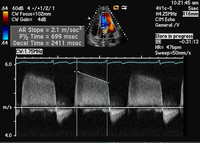

Continuous wave Doppler of the regurgitant jet demonstrating pressure half-time of the aortic regurgitant velocity

From the collections of Dr Sanjeev Wasson and Dr Nishant Kalra; used with permission